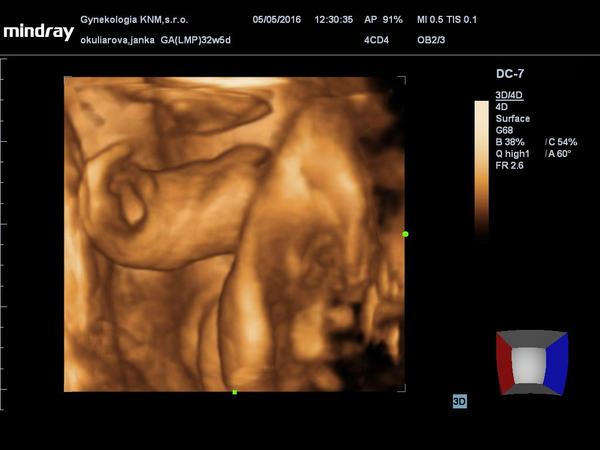

Pomýlil sa doktor pri určení pohlavia na 3D sone v 20 týždni?

Ahojte prosim o radu...dnes som 13+2 tt a bola som na ult... Mame doma chlapceka moc sme tuzili po princeznicke...dr mi robil aj 3D a bolo medzi nozkami videt pipika...ja som tam hned zbadala a ja ze pipik a dr sa smial ze my zeny vsade vidime pipikov xi,no ale moj vnutorny pocit stale od zac je ze dievca,byva mi hrozne zle to pri malom nebolo....takze dr pov ze "pracovne"je to chlapcek....

Myslite ze je nejaka sanca ze by to mohlo byt dievca????

@ernuska296 ahoj, ako tu mozes citat, lekari sa vedia pomylit, dokonca aj pri 3D a 4D sone, dokonca si mozu pomylit dievca s chlapcom i chlapca s dievcatom.... cize istotu budeme mat az pri porode, alebo potom pri krvynch testoch, ci odbere plodovej vody... (ale to ked zena skutocne "nemusi" absolvovat, nech do toho nejde)... ak si precitas diskusiu, su tu zeny, ktore citili, robili si vypocty a nakoniec to bolo inak.... cize odpoved na tvoju otazku je, ano, z ne/ocakavaneho chlapca moze byt ne/ocakavane pri porode dievca a naopak 😀

@adrianka22 na urcenie pohlavia je vzdy lepsie 2d sono nam sa na zaciatku dr zmylila vraj chlapec neverila som vo vnutfi som itila ze to bude dievca.a tak aj je dalsie ultrazvuky ukazali ze je to dievcatko.neda sa ti ta foto este raz odfotit lepsie.?

Ja mam 3 chlapcov a pri 4 som bola na 4d sone ked nam doktor povedal ze to bude dievcatko sme nemohli tomu uverit stale do okola sme sa pyzali ci sa nepomylil a on ze sa nemyli.este dalsich doktorov som sa pytala v nemocnici aj ty potvrdili dievcatko a naozaj nasa princezna bude mat za chvilu 3 mesiaciky.